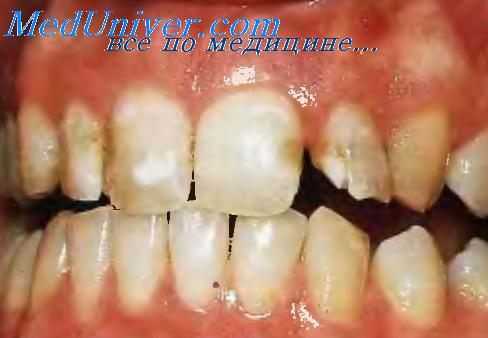

При осмотре определяют цвет, количество и локализацию пятен. Для кариеса характерны единичные белые и пигментированные пятна эмали в области шеек, фиссур и контактных поверхностей зубов. Может быть изменение цвета эмали и над зоной дефекта.

- На стадии кариозного пятна происходит помутнение эмали зуба. Видимых разрушений твердых тканей зуба нет, инструментальное обследование зондом малоинформативно, так как на этом этапе еще нет признаков изменения структуры твердых тканей зуба. Иногда возможен регресс пятна, причины этого явления не выяснены, однако стоматологи связывают самовыздоровление с активизацией иммунной системы.

- Вторая форма кариеса – это поверхностный кариес. На поверхности зуба появляется темная пигментация, во время инструментального осмотра в зоне пигментации выявляется размягчение эмали. Иногда уже на стадии поверхностного кариеса в разрушительный процесс вовлекаются все слои зубной эмали. Но обычно дефект ограничен и не выходит за пределы эмали. Кариозное поражение выглядит как грязно-серое или коричневое пятно с шероховатым дном.

- Прогрессирующая. Характеризуется образованием белых и светло-желтых пятен на зубах, которые вызывают оскомину и дискомфорт. Начальный кариозный процесс протекает остро, зачастую вовремя не диагностируется. Стадия пятна существует небольшой период времени, через 2-3 недели переходит в поверхностный кариес.

Клиническая симптоматика мало выражена, характеризуется образованием на зубе пятна круглой или овальной формы. Очаг деминерализации гладкий, может иметь разный оттенок от бело-желтого до темно-коричневого. Сначала появляется светлое пятнышко, безболезненное или несколько болезненное в зависимости от индивидуальной чувствительности. Во время употребления кислой и сладкой пищи отмечается чувство оскомины, дискомфорт. Через несколько месяцев очаговая деминерализация переходит в поверхностный кариес или насыщается пигментами полости рта и приобретает коричневый цвет. Как будет развиваться начальный процесс, зависит от кариесогенной ситуации, наличия общих и местных факторов болезни. Темный очаг поражения полностью безболезненный, пациенты жалуются на наличие эстетического дефекта.